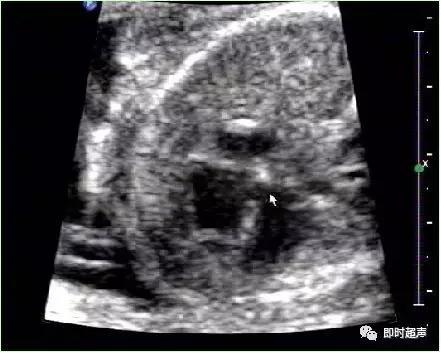

五、心室内强光斑(EIF)

心室内强回声光斑或心内灶性强回声

胎儿心室强光点指直径为1~6mm的斑状、灶状或条索状的结构,其回声强度与周围骨结构接近,可为单发,多发,以左室乳头肌处最常见,是妊娠期较常见超声表现。随孕期增加逐渐减弱,最迟在1岁内消失。

形成原因可能是:

心室内腱索增厚而形成的强回声反射;乳头肌中央矿物质的沉积、钙化,这可能是乳头肌内冠状动脉末梢分支早期缺血性改变。

病理学可见乳头肌处的微钙化灶,可能与胎儿染色体异常有关。大多数的研究报道单纯性的心室强光点常无临床意义。

超声检查胎儿心室强光点临床意义

✔ 低风险胎儿如单独出现EIF而无其他异常超声表现时,临床意义不大,可超声随访,不必进一步做有创性检查。

✔ 高风险胎儿即使单独出现EIF,其染色体异常的风险也增加,建议遗传咨询,结合临床多因素谨慎处理。

✔ 低风险组胎儿检出EIF,同时合并有多项其他超声软标志时,其染色体异常的风险增加。

✔ 大多数的研究报道单纯性的心室强光点常无临床意义,超声检查所见的胎儿心脏发育过程中的一种变异。